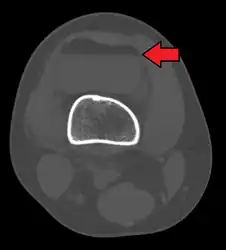

3D reconstruction of a CT image of a tibial plateau fracture

Lipohemarthrosis due to a tibial plateau fracture